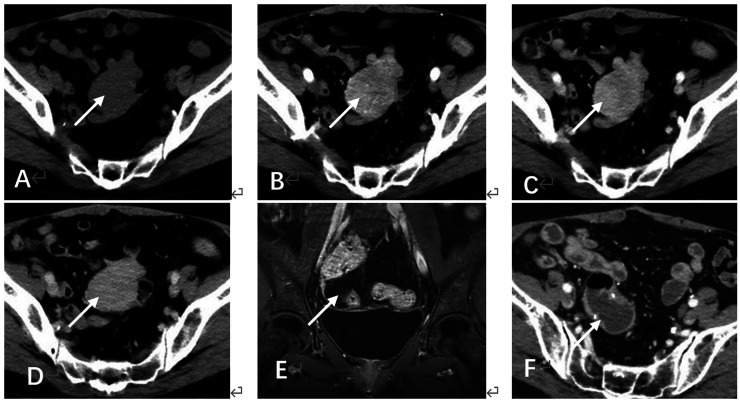

成人型卵巢颗粒细胞瘤是一种罕见的低级别恶性肿瘤,其特点是复发晚,临床表现不典型。本研究报告2例复发的成人型卵巢颗粒细胞瘤,具有不同的时间线和解剖部位,其中1例术后两次复发。我们分析其影像学特征、手术处理、组织病理学、术后随访,并复习相关文献。这些病例强调了长期随访的重要性,提高了对罕见复发部位的认识,强调了影像学的诊断价值和对成人型卵巢颗粒细胞瘤患者个性化监测策略的必要性。

Adult-type ovarian granulosa cell tumors are rare low-grade malignancies characterized by late recurrence and atypical clinical manifestations. This study reports two cases of recurrent adult-type ovarian granulosa cell tumor with distinct timelines and anatomical sites, including one case with two postoperative recurrences. We analyze their imaging features, surgical management, histopathology, postoperative follow-up, and review relevant literature. These cases highlight the importance of long-term follow-up and raise awareness of rare recurrence sites, emphasizing the diagnostic value of imaging and the need for individualized surveillance strategies in adult-type ovarian granulosa cell tumor patients.